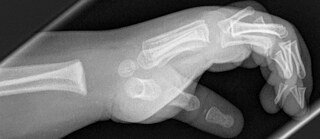

Strahlen, die Menschen durchleuchten.

CC0

Richtig. Wilhelm Conrad Röntgen entdeckte die Strahlen eher durch Zufall. In Deutschland werden sie heute Röntgenstrahlen genannt.